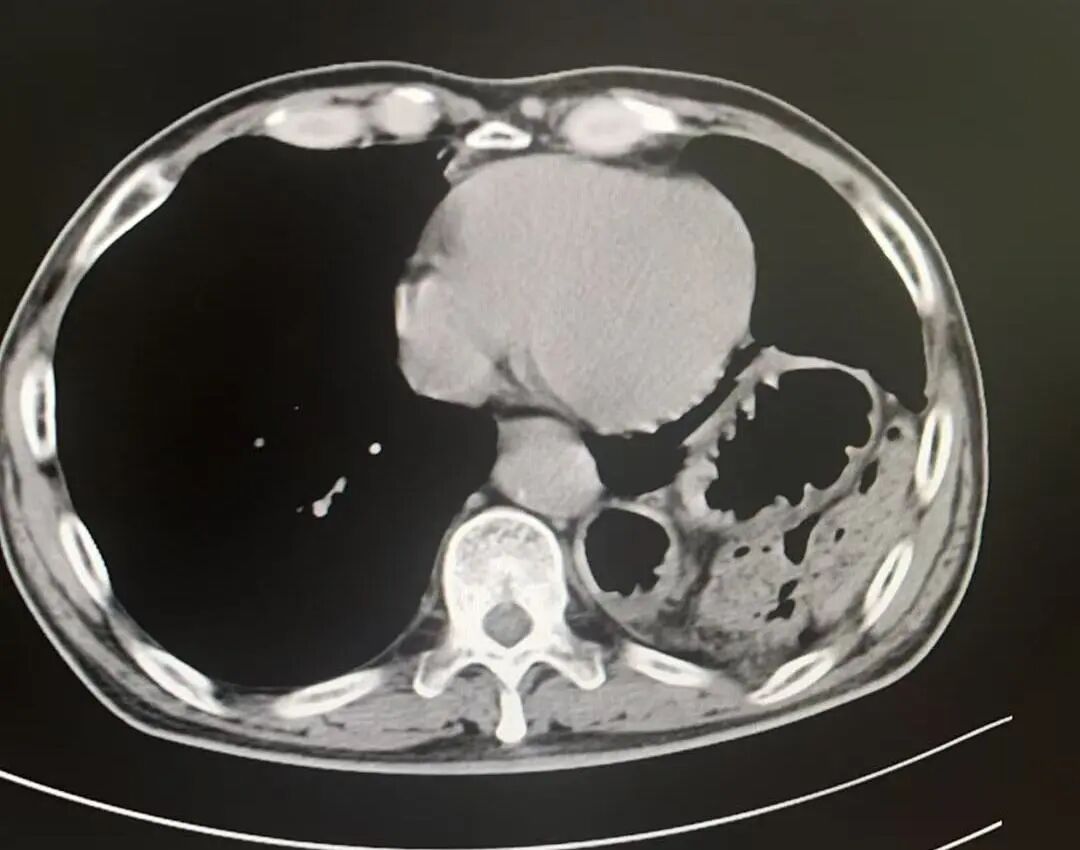

术后影像

膈疝修补如拆“定时炸弹”,需松解粘连、归位脏器、修复缺损三步精准到位。团队采用阶梯策略,在确保手术效果的同时最大程度降低风险、减少创伤。术后,刘大爷的症状迅速缓解,现已康复出院,重归正常生活。

术中发现胃、结肠、小肠及脾脏疝入胸腔且与周围组织严重粘连,部分脏器难以通过微创完全复位。孙振教授果断决策,通过10厘米切口精细分离粘连,成功还纳全部脏器并牢固修补缺损,杜绝复发隐患。